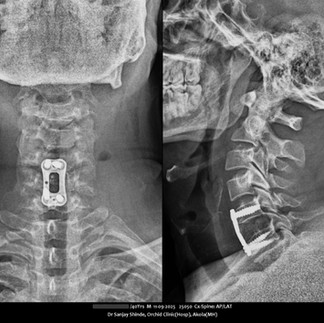

D. Spine Problems

The spine supports the body and protects the spinal cord. Conditions like degenerative disc disease, herniated discs, spinal stenosis, and scoliosis can affect quality of life. Advances in medical technology now offer effective management options.

Degenerative Disc Disease

Degenerative disc disease involves the deterioration of intervertebral discs, causing pain and reduced mobility. New treatments like minimally invasive spine surgery and artificial disc replacement aim to relieve pain and maintain spinal function, promoting quicker recovery.